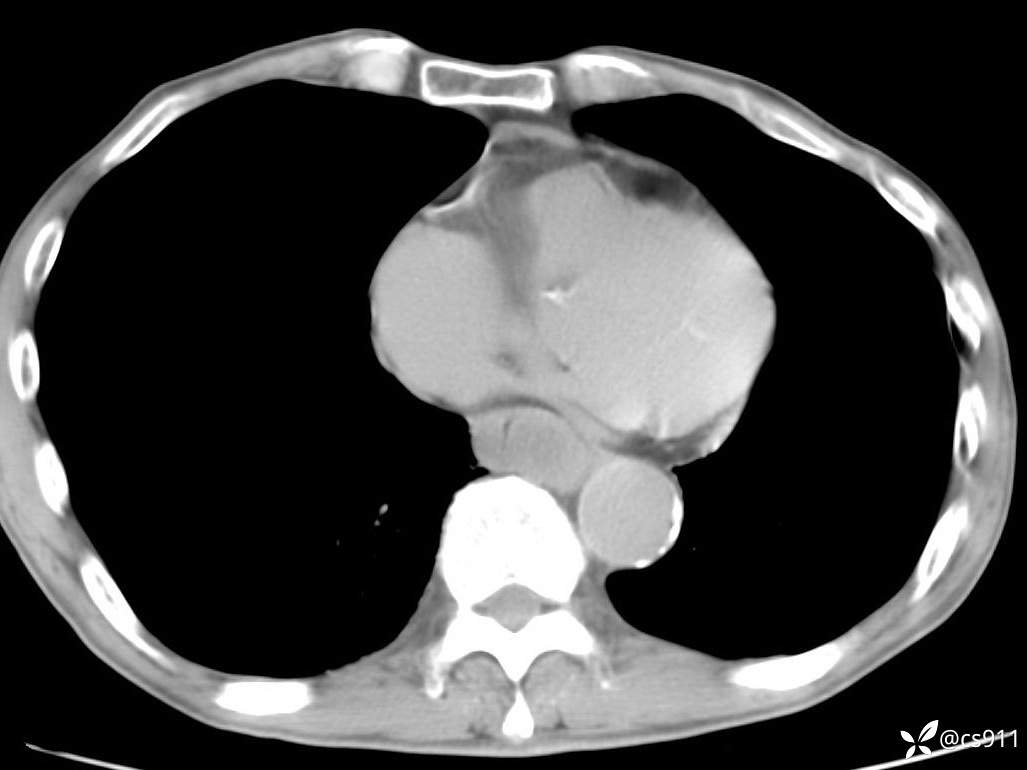

急腹症之急诊CT,原因?答案公布

男,77岁,腹痛、腹胀伴恶心呕吐1天。呕吐胃内容物,非喷射性呕吐,有咖啡色样胃内容物,诉有胃穿孔病史。查体:全腹平,下腹部压痛,全腹无反跳痛,叩诊呈浊音,移动性浊音阴性,肠鸣音减弱,1-2次/分。肛检:直肠未扪及明显肿物,可触及大量粪块。

T 36.6℃ P 80次/分 R 26次/分 BP 100/60mmHg

白细胞(WBC) H 14.55 10e9/L 4-10

中性粒细胞百分率(NEUT%) H 85.7 % 40-75

血淀粉酶(AMY) HH 1859 U/L 35-135

癌胚抗原(CEA) H 27.44 ng/ml 0-5

呕吐物 潜血试验 * 阳性 阴性

患者轮椅入室检查神志清楚, 能配合摆位和呼吸